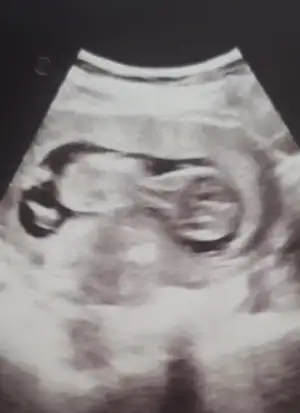

14 haftaligiz tahmin alabilirmiyim

• IMG_20210908_145915.webp

IMG_20210908_145915.webp

16,4 KB · Görüntüleme: 79